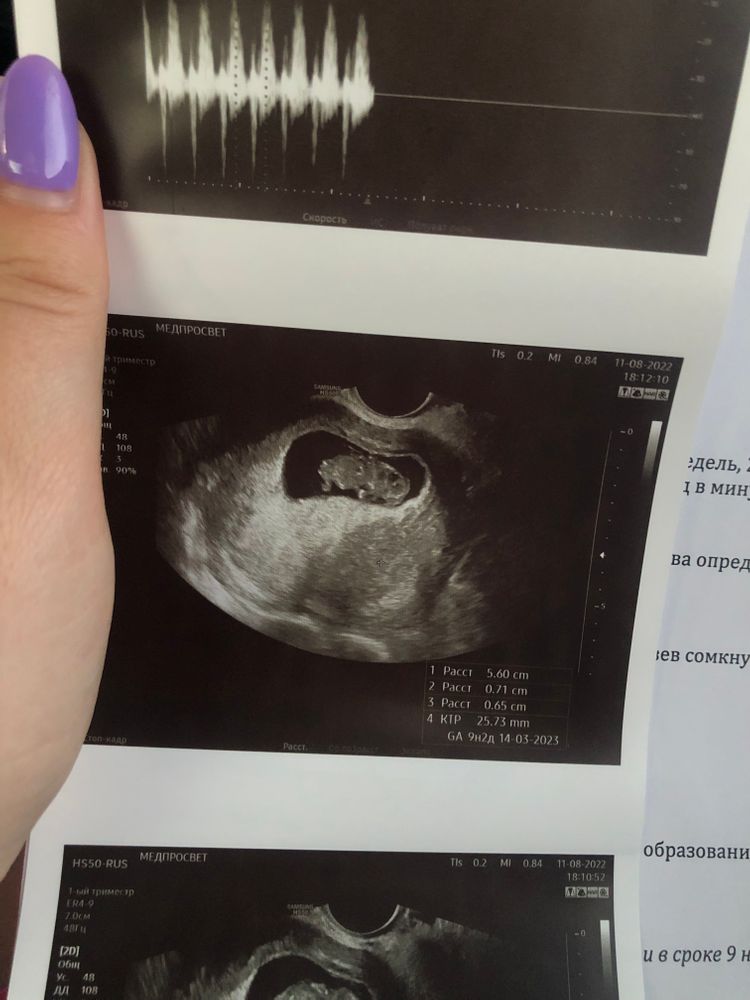

Стал сегодня живот немного болеть, даже можно сказать тянуть и покалывать то там, то тут. Мне врач говорила, если что-то беспокоит, звони, приходи, любой врач примет (мой врач в отпуске сама до 12 числа, но предупредила меня до отпуска, что делать в случае чего). Я звоню в ЖК, хочу записаться или просто подойти к доктору к любому (хотела узнать в какое время мне можно подойти, чтобы туда не переться впустую), чтобы посмотрели, сделали узи, ну или сказали чем снять спазм. Берет трубку админ в регистратуре, и я ей объясняю ситуацию: «Тянет живот, 10ая неделя беременности, можно мне сегодня попасть к врачу?», на что она мне отвечает: «Вызывайте скорую». Я мягко говоря в шоке, человек без мед.образования вместо того, чтобы записать, предложить когда подойти и т.д. мне говорит что делать. Или просто ответственность с себя снимают в ЖК, чтобы лишний раз не париться. Конечно же я позвонила в мед.центр и записалась к платному врачу, к которому ходила на 5ой неделе. Приехала, сделал узи, с малышом все хорошо, растет как положено, ктр 26мм. Со мной тоже все хорошо, увидел гематому 7 мм🤷🏻♀️ поэтому и тянет живот. Нахожусь на больничном, никуда не хожу, много лежу, не скачу, на работу не езжу, откуда взялась непонятно.

Ну и немножко фоточек малыша прикреплю😍 Сердечко дали послушать, так громко и часто бьется😍 (ЧСС 189 уд/минуту)